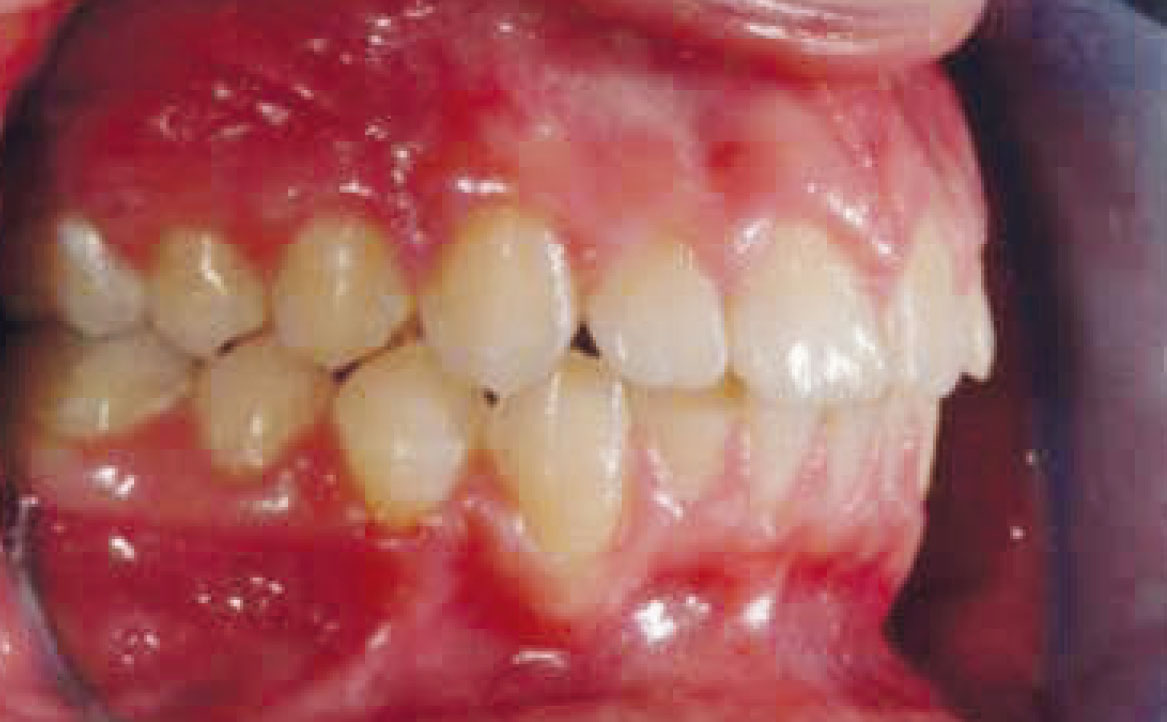

La buona collaborazione della paziente ha consentito di ottenere un buon avanzamento mandibolare, la correzione delle classi canina e molare (ben evidenti nelle fotografie intra orali mostrate in fig. 15 e 17). Il morso aperto residuo verrà corretto mediante immediato inizio della terapia ortodontica fissa al fine di abbreviare la durata complessiva del trattamento.

La paziente ha collaborato durante la fase ortodontica così come precedentemente in quella ortopedica, il che ha permesso di ottenere un buon allineamento dentale, una buona occlusione ed una soddisfacente macro e mini-estetica.

La terza fase, ossia quella eseguita mediante l’apparecchiatura ortodontica fissa, ha consentito di ottenere un buon allineamento dentario e affinare l’intercuspidazione tra l’arcata superiore e inferiore.